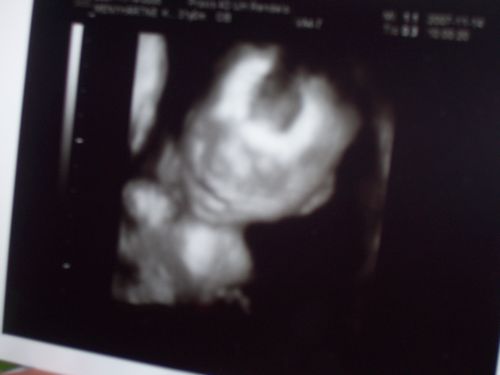

mi is voltunk 12. héten de akkor még csak 48mm volt a csöppem ezért rá egy hétre ujra és ime a képen a kis akrobata már 64 mm..majdnem 2 cm egy hét alatt